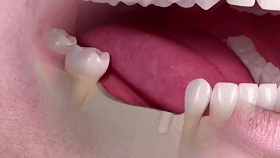

种植牙是医学界公认的理想修复方式,被誉为“人类的第三副牙”。相比活动假牙不舒服、难清洗、容易引起口腔黏膜病变,种植牙更稳固耐用,舒适美观,咀嚼功能好,一次种植,终生受用。种植牙不仅是中老年人的专利,年轻人因意外、牙病等造成牙齿缺失,也能够通过种植牙进行修复治疗,重获美丽笑容。

(多颗种植示例)